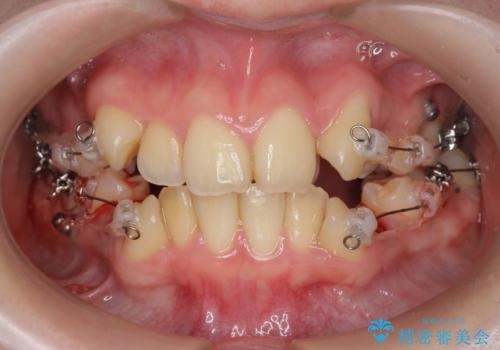

歯並びのせいで歯ブラシがしづらい マルチブラケットを用いた抜歯矯正

- 歯並びのがたつきにより歯ブラシがしづらく、今後虫歯になってしまう不安から、矯正治療を希望されて来院されました。

歯を並べるにはスペースが不足しているため、小臼歯の抜歯を4本行うマルチブラケット矯正による治療を計画します。

治療後は非常に歯ブラシがしやすくなったと、治療結果に満足いただくことができました。